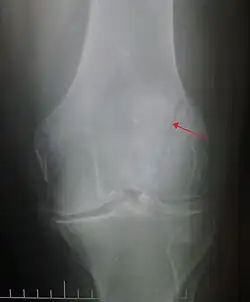

Patella fracture

A patella fracture is a break of the kneecap.[1] Symptoms include pain, swelling, and bruising to the front of the knee.[1] A person may also be unable to walk.[1] Complications may include injury to the tibia, femur, or knee ligaments.[2]

It typically results from a hard blow to the front of the knee or falling on the knee.[1]The patella can also be fractured indirectly. For example, a sudden contraction of the quadriceps muscle in the knee can pull apart the patella.[1]Diagnosis is based on symptoms and confirmed with X-rays.[3] In children an MRI may be required.[3]

Diagnosis is based on symptoms and confirmed with X-rays.[3] In children an MRI may be required.[3]